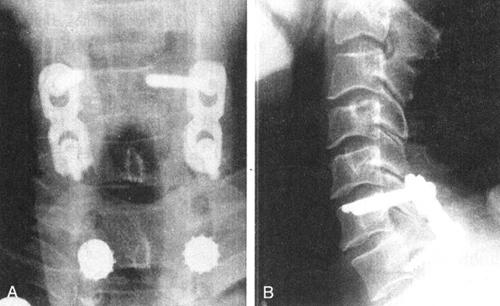

图13-29 C6右侧椎弓根与椎体连接处骨折引起C6前脱位,术中C6用椎弓根螺钉固定,C7用侧块螺钉。C6右侧椎弓根钉可以固定骨折块